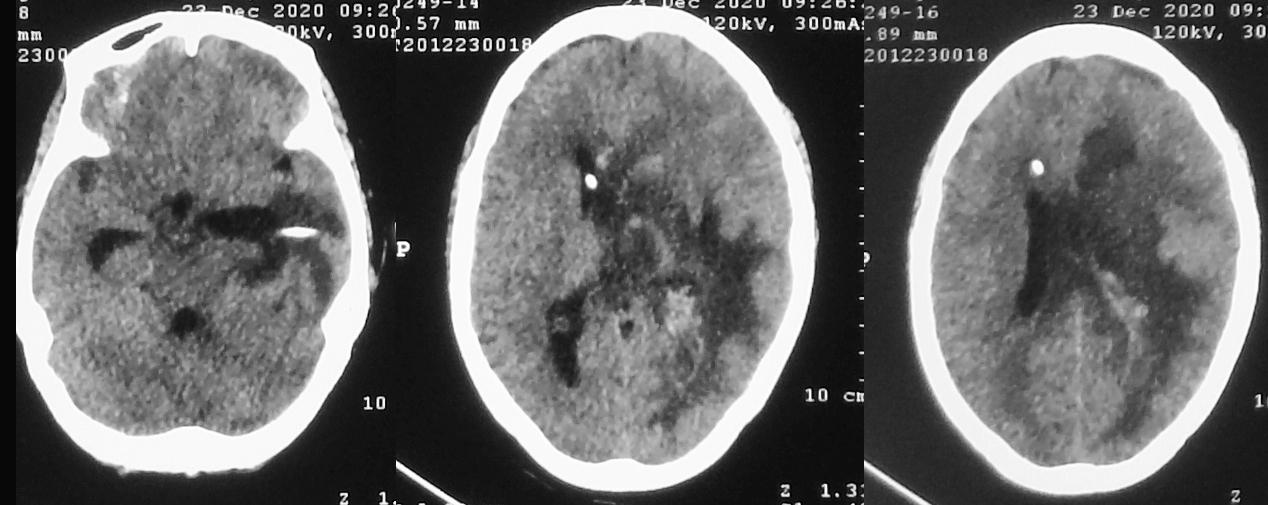

患者体温正常,仍呈朦胧状态,可自动睁眼,刺激肢体可活动。脓肿清除术后第13天,左侧颞角外引流术后第12天,右侧脑室穿刺术后10天,即2020年12月21日,复查头颅核磁( 图-16 )见脑室缩小,丘脑脓肿病灶缩小,左侧脑室枕角和小脑表面的强化灶消失,提示颅内感染好转。

图-16: 2020年12月21日头增强核磁

脑脓肿清除术后第15天,左侧颞角外引流术后第14天,右侧脑室穿刺术后12天,即2020年12月23日,复查头颅CT见术区脑水肿较前(2020年12月16日)减轻( 图-17 )。

图-17: 2020年12月23日头CT